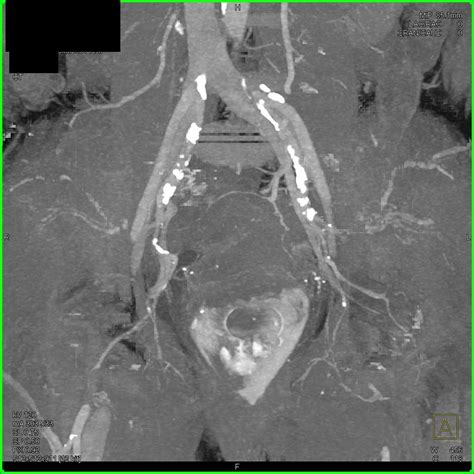

• Imaging studies, such as X-rays, CT scans, or MRI